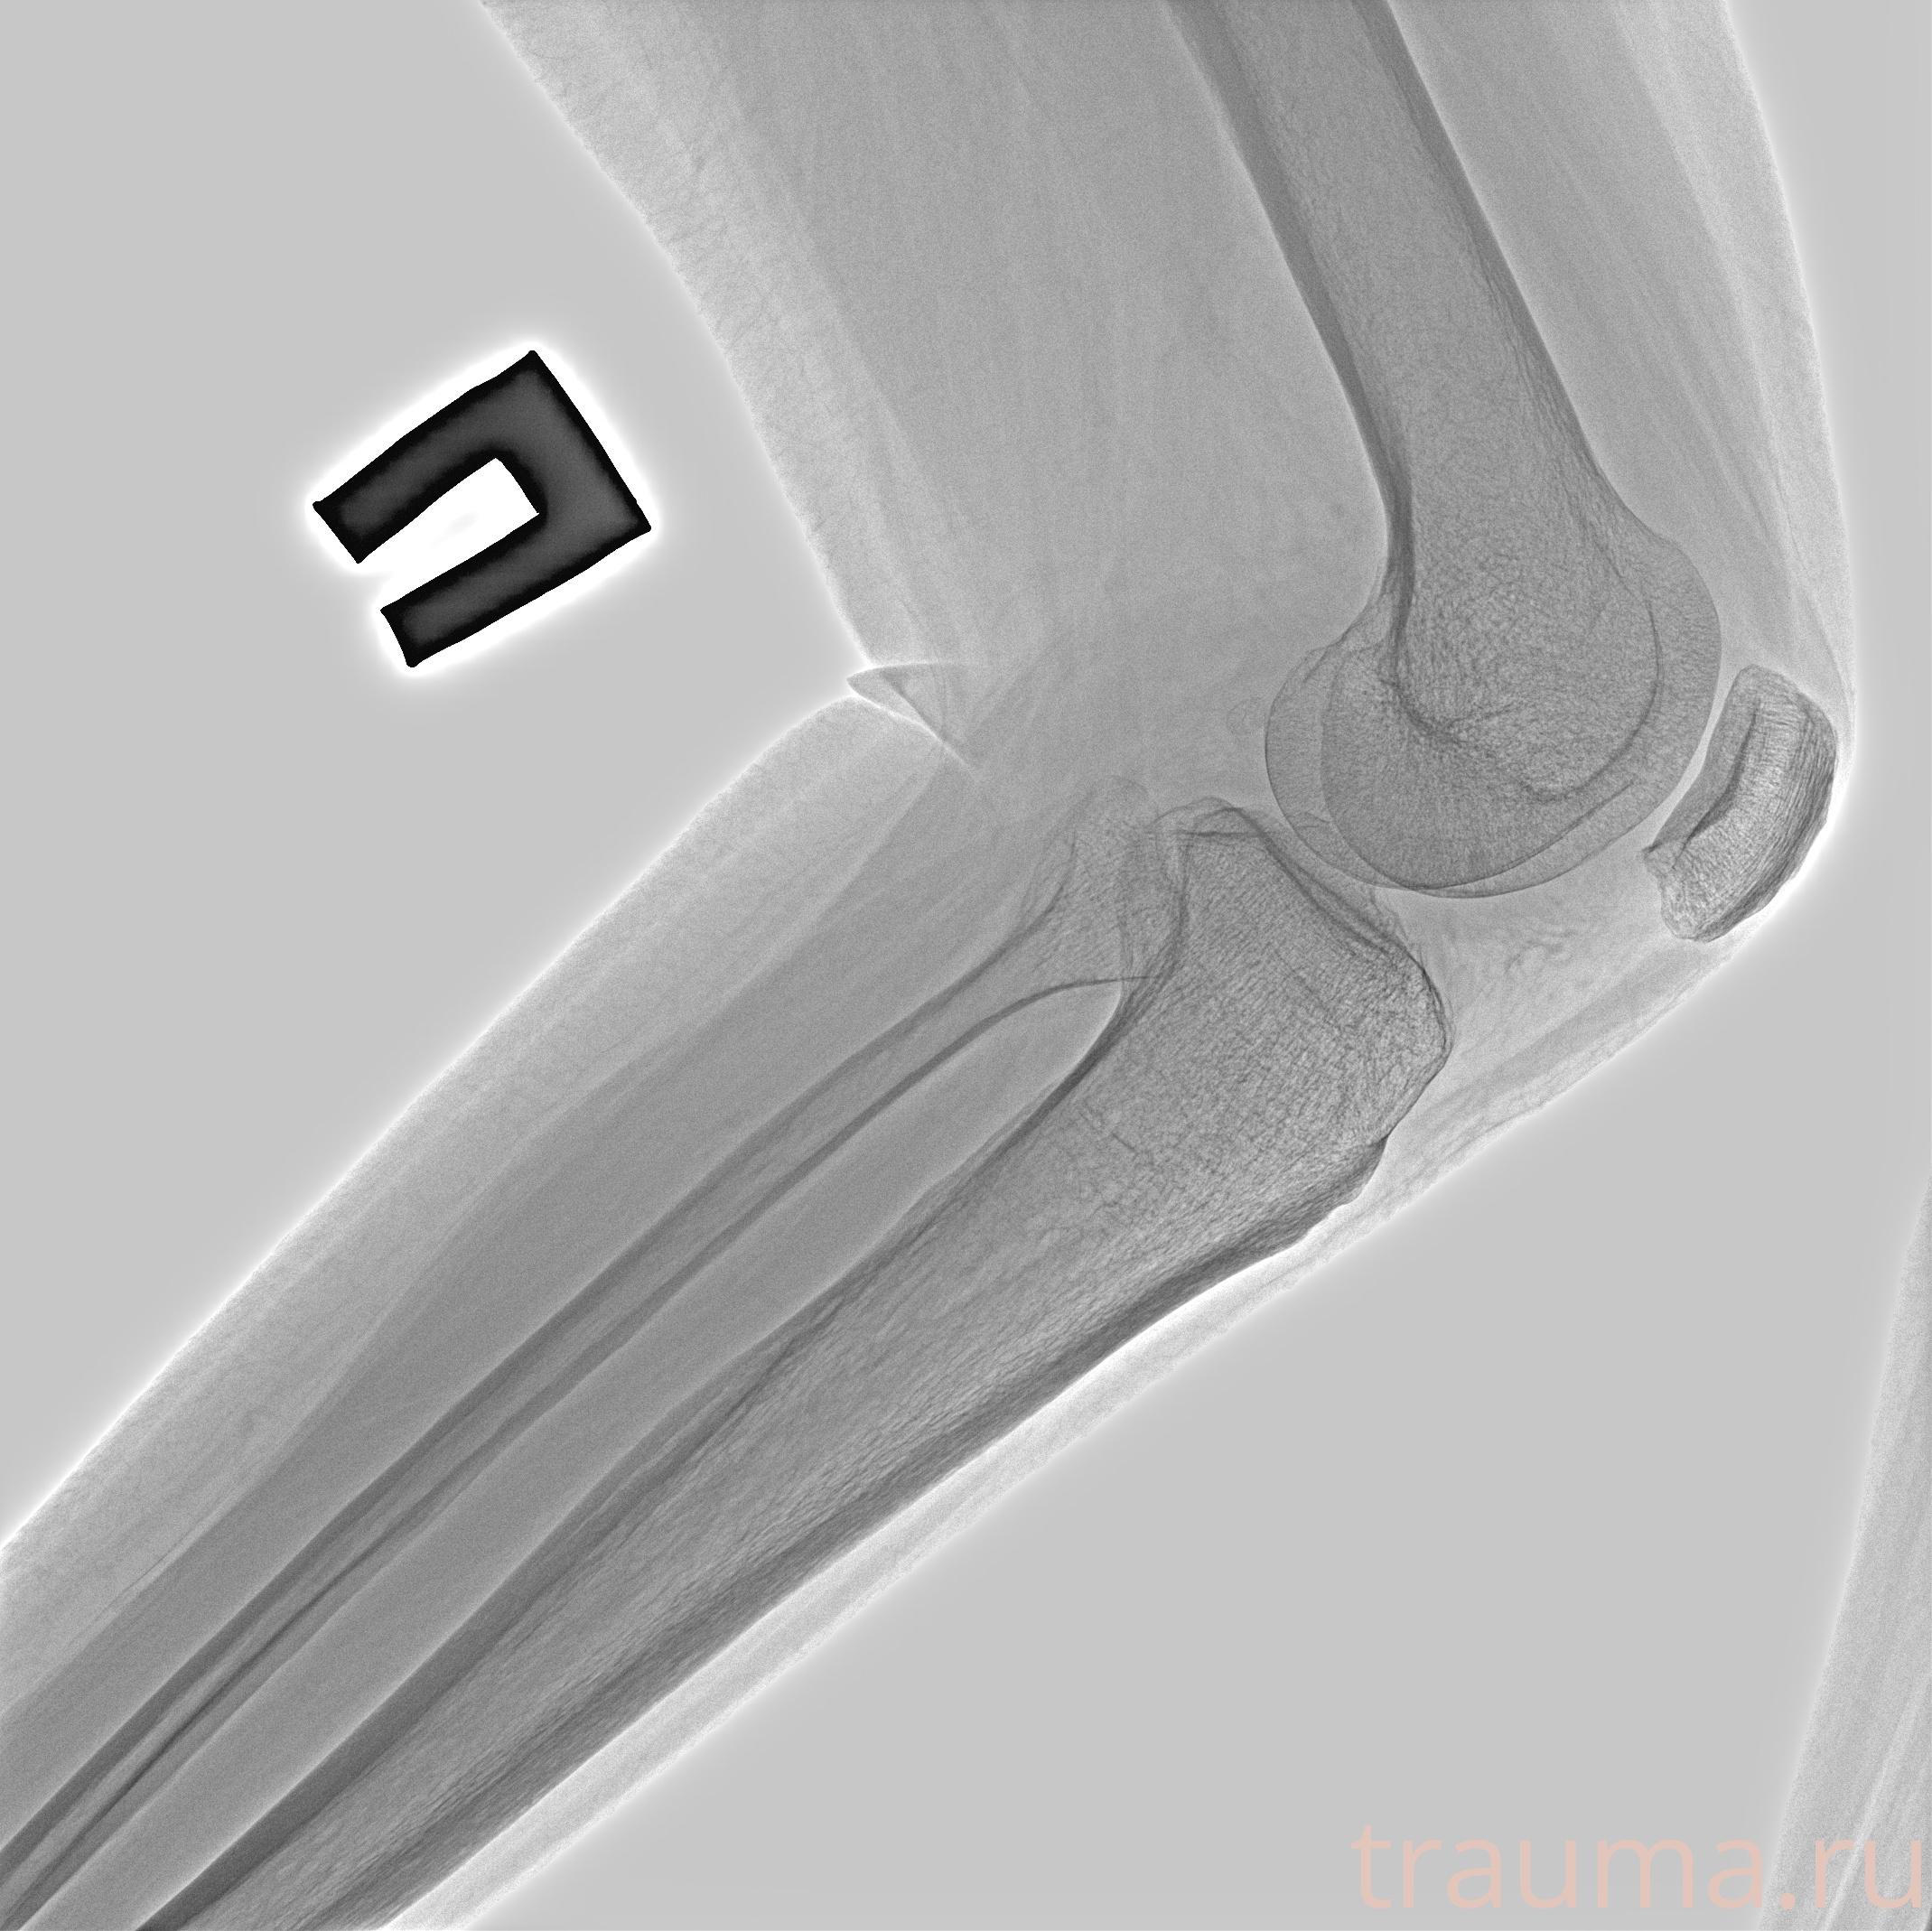

Рентгенограммы

Рентген на дому: по вашему адресу приезжает врач-рентгенолог, травматолог-ортопед с мобильным рентгеновским аппаратом, проводит диагностику травмы или заболевания, делает необходимые рентгенограммы, дает рекомендации по дальнейшему лечению. Получить качественные снимки в домашних условиях возможно благодаря уникальной методике, разработанной МосРентген Центром для института  Склифосовского